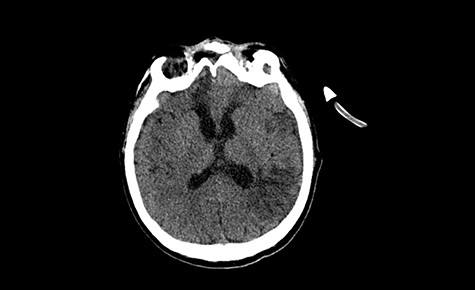

Head CT after polypectomy—seen sphenoid sinus and both maxillary sinuses filled with blood. (Department of Neurosurgery own material).

In described case, a head CT scan after polypectomy confirmed the subarachnoid hemorrhage (Fig. 1). In addition, the presence of air in the ventricular system was visible, and presence of defects of the upper left orbital wall and ethmoid on both sides (Fig. 3). In the CT scan sphenoid sinus, frontal and ethmoidal sinuses on both sides and right maxillary sinus airless, filled with blood and soft tissue. The changes also concerned the lateral part of the left maxillary sinus (Fig. 4).

The present bone defects were most probably caused by the development of osteomalytic foci as a consequence of the spread of the inflammatory process within the diploe of flat skeletal skull bones, in the course of chronic rhinosinusitis. Both underestimating the severity of complaints in the course of chronic rhinosinusitis and delaying the implementation of surgical treatment led to massive bone destruction, which had an impact on the development of further complications after polypectomy (including subarachnoid hemorrhage). Performed angio-CT excluded any malformations and the probable cause of subarachnoid hemorrhage due to rupture of the aneurysm. Considering the radiological picture and the condition of the patient, it can be concluded that the persistent inflammatory process within sinuses led to dehsomination and subsequent bleeding into the subarachnoid space through discontinuity in the bone structure of the sinuses and orbits.